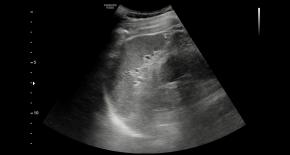

Comments Although the hepatic parenchyma may initially appear coarse, the liver actually shows numerous tiny hyperechoic foci with comet-tail artifacts scattered throughout the parenchyma. In addition, there are no accompanying findings suggestive of chronic liver disease or cirrhosis, such as liver contour blunting, surface nodularity, liver volume redistribution, dilatation of the portal vein, or splenomegaly.

• The CAP value of 227 dB/m and liver stiffness measurement of 4.4 kPa suggest no steatosis (S0) and no fibrosis (F0), respectively.